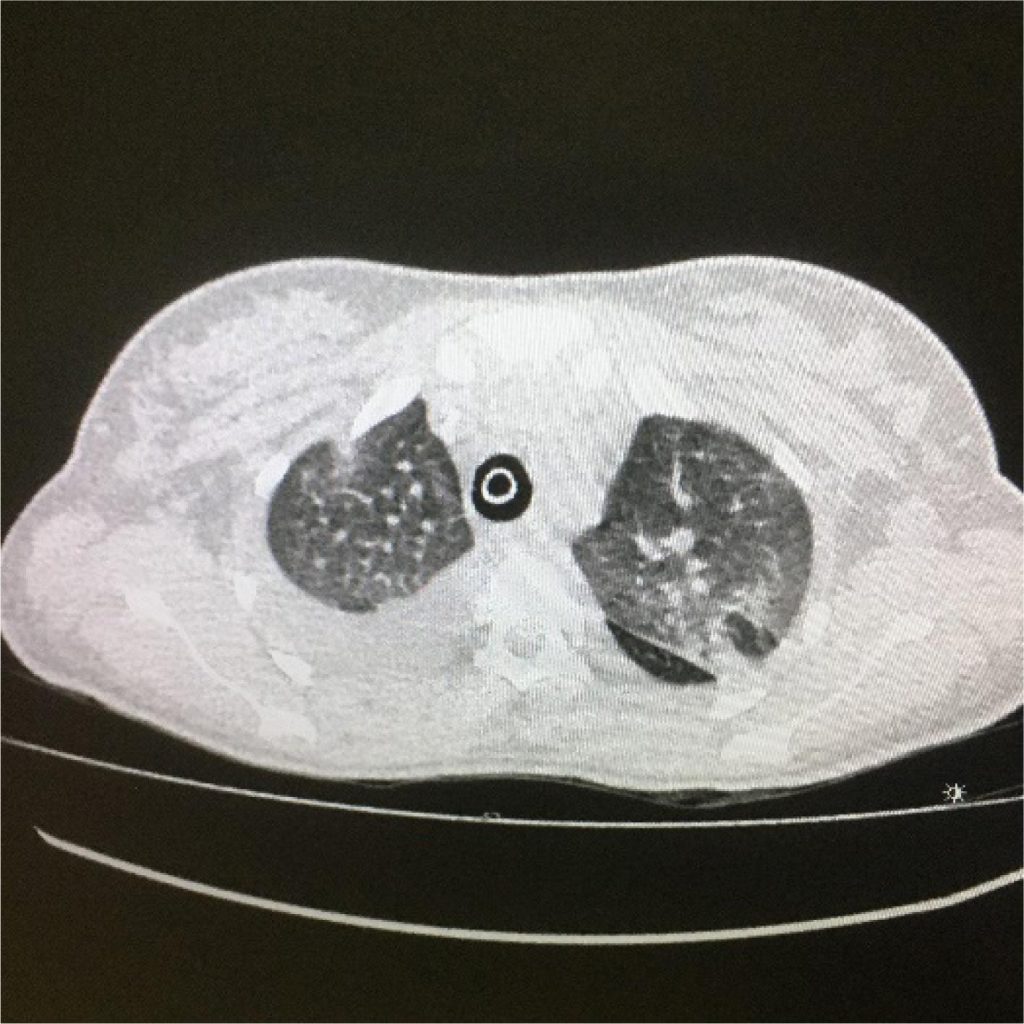

Volume Vascular Pulmonar Estimado por Software Automatizado é um Preditor de Mortalidade após Embolia Pulmonar Aguda

Leonardo Soriano et al.

MINIEDITORIAL

Mais Estudos devem ser Realizados sobre o Volume Vascular Pulmonar Estimado por Software Automatizado em Embolia Pulmonar Aguda

Marcelo Souto Nacif